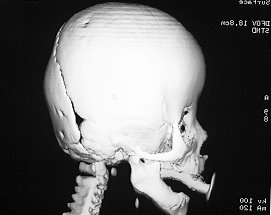

Coronal

(12-29% of synostoses)

• Bilateral

• brachycephaly (short AP dimension)

• acrocephaly (pointed head, vertically)

• equal male and female association

• Unilateral

• frontal plagiocephaly

• flattened ipselateral forehead

• compensatory bulge on contralateral forehead

• ipselateral eyebrow elevation

• prominent contralateral ear